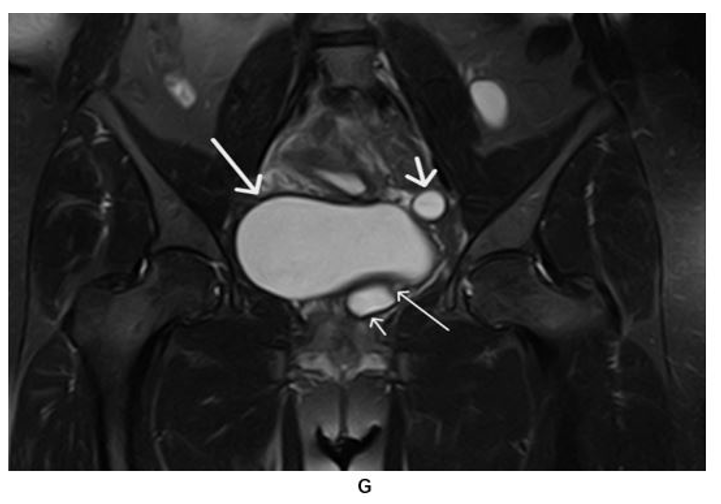

Figure 7: Pelvic MR Non-Enhanced Coronal STIR (G) Image: Gartner’s Duct Cyst (Short Thin Arrow), Urinary Bladder (Long Thick Arrow), Tubular structure (Short Thick Arrow), Tubular Structure Opening into Gartner’s Duct Cyst (Long thin Arrow)